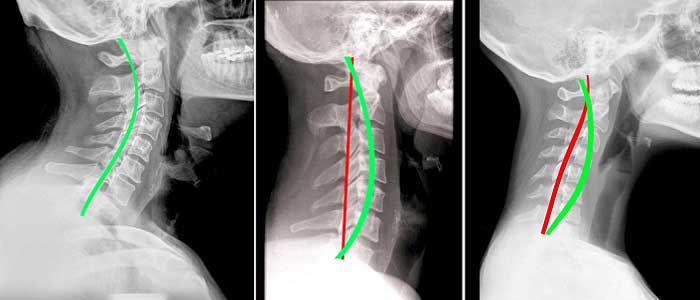

Özellikle de genç nüfusta daha çok görülmektedir. Normal şartla C harfine benzeyen omurga, zaman içinde I harfine benzer hale gelmektedir. İnsan vücudunun duruşunu ciddi şekilde bozan hastalık kişiyi rahatsız eder. Hastalığın teşhisi kısa sürede mümkündür ama tedavi çok önemlidir. Tedavinin aksatılması daha ciddi sorunlarla karşı karşıya bırakılabilir.

Boyun düzleşmesi sonradan gelişen fiziksel bir hastalıktır. C şeklindeki boyun bölgesi I şeklini aldığında boyun düzleşmesinden söz edilir. İnsanlarda omurganın dizilimi, genişliği, şekli kişiye özeldir. Boyun bölgesindeki C şekli insanlardaki tek ortak noktadır denebilir. Boyun düzleşmesi hastalığının altında yumuşak disklerden oluşan omurganın kayması ve özelliğini kaybetmesi yatmaktadır.

Şikayetlerinizle birlikte sağlık merkezine başvurduğunuzda uzman fiziksel muayene yapacak ve bazı tetkikler isteyecektir. Fiziki muayene aslında yeterli bilgiyi vermektedir ama kesin tanı için röntgen ya da MR tercih edilmelidir. Röntgen ya da MR ile net bir şekilde teşhis koyulabilir. Fiziki muayenede doktor öncelikle boynun sağa, sola, öne ve arkaya doğru hareketlerine bakmaktadır. Doktor boyna ve çevresine dokunduğunda hastanın verdiği tepkilerle ölçüm yapılabilir. Boyuna bağlı olarak kollarda, ellerde ve ayaklarda oluşabilecek güç kayıplarını anlayabilmek için tepki ölçümü de fiziksel muayenenin bir parçasıdır.